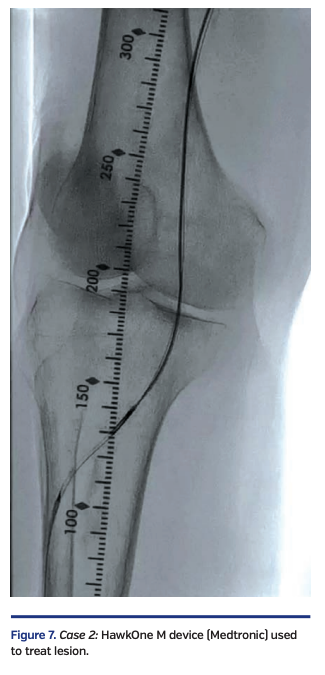

The Enteer wire was exchanged out for a V-18 wire that was subsequently externalized via the right common femoral artery sheath. Over an antegrade Fielder FC wire, intravascular ultrasound (IVUS) evaluation was performed with an .014-inch IVUS catheter, followed by directional atherectomy with a HawkOne M device (Medtronic) (Figure 7).